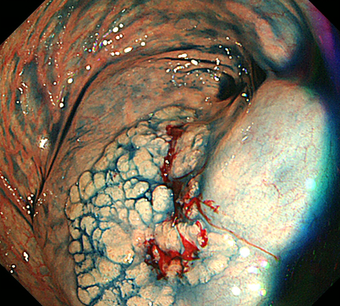

3)内視鏡的粘膜下層剥離術(ESD)

2cmを越える大きな腫瘍では、通常の内視鏡的ポリープ切除や粘膜切除術では一度に切除することが難しくなります。何度かに分割して切除すると再発率が高いため、内視鏡的粘膜下層剥離術(ESD)で腫瘍全体を一度に切除する方法を行います。ESDではヒアルロン酸溶液などを粘膜下に注入し病変を盛り上げてから、ナイフで少しずつ病変を削り取って切除します。現在のところ大腸がんに対するESD は高度先進医療実施施設でのみ実施が可能です。大きな潰瘍ができるため出血や穿孔の危険性が高くなるため、通常1週間くらいの入院が必要です。